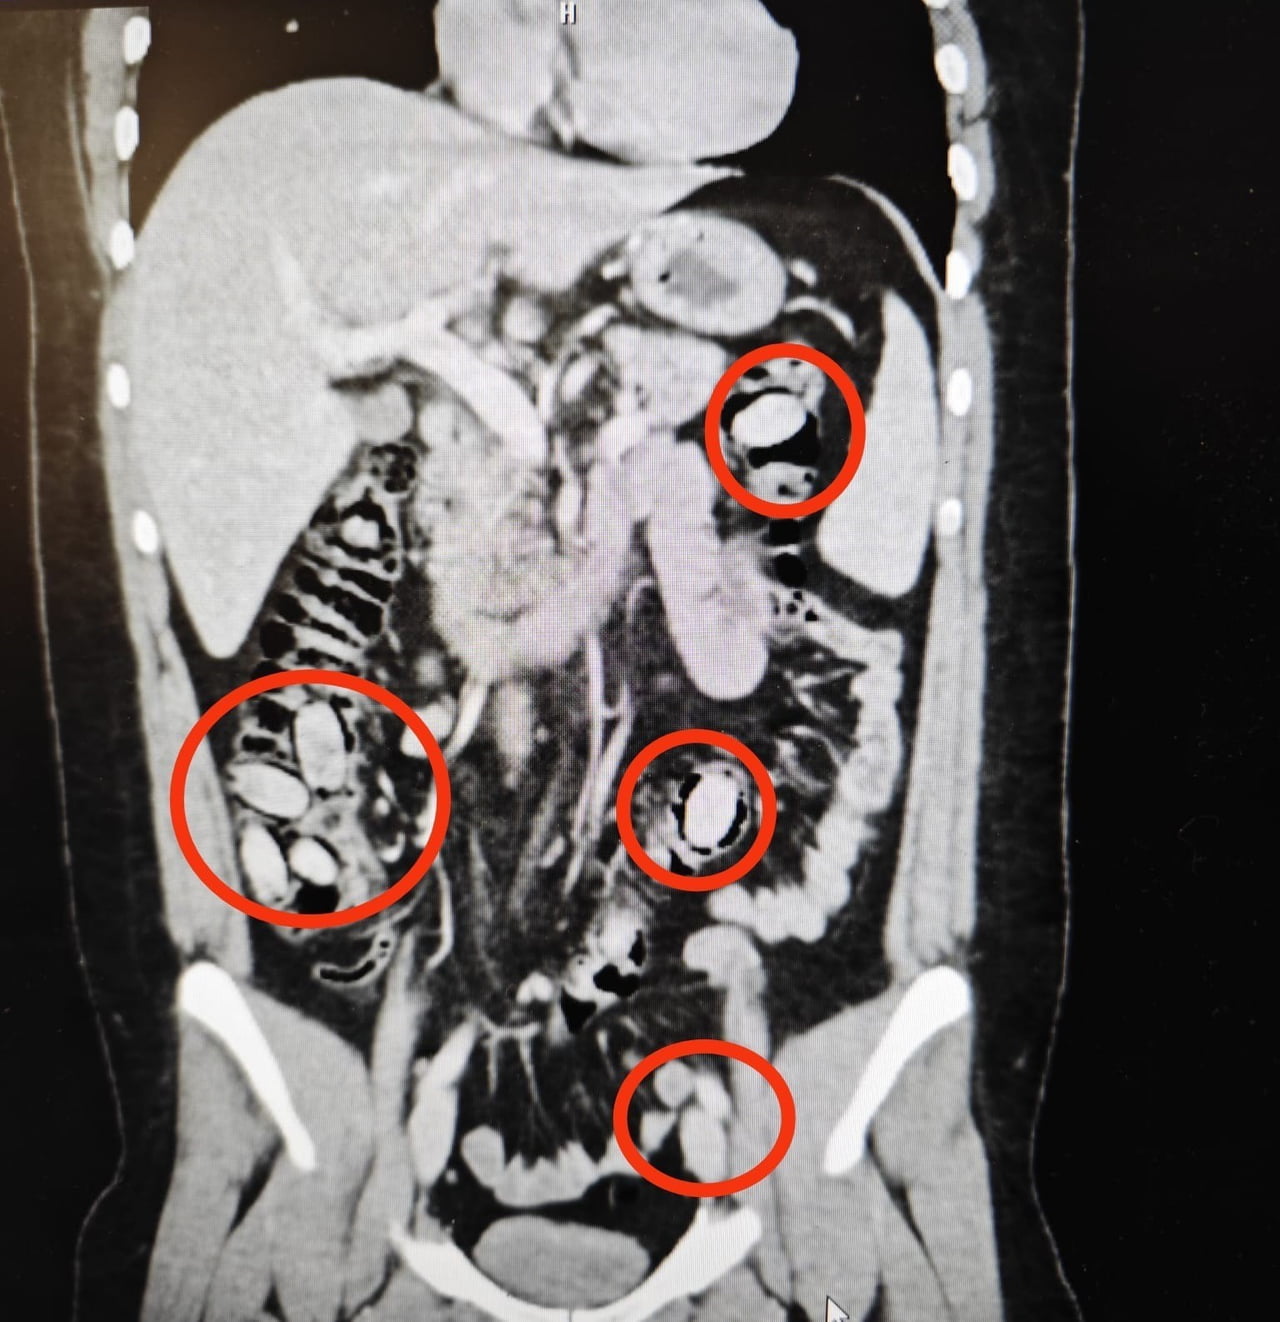

Yurtdışından Eskişehir'e giriş yapan S.A. (25), kent girişindeki çevirme noktasında polis ekiplerinin dikkati sayesinde durduruldu. Yapılan ilk incelemede şüpheli davranışlar üzerine hastaneye sevk edilen şahıs hakkında detaylı tetkikler yapıldı.

Hastanede gerçekleştirilen tetkikler sonucunda şahsın yutmak suretiyle midesinde 44 kapsül metamfetamin taşıdığı tespit edildi.

Cerrahi müdahale ile söz konusu kapsüller şahsın bedeninden çıkarıldı. Tedavisinin tamamlanmasının ardından çıkarıldığı mahkemece tutuklandı.